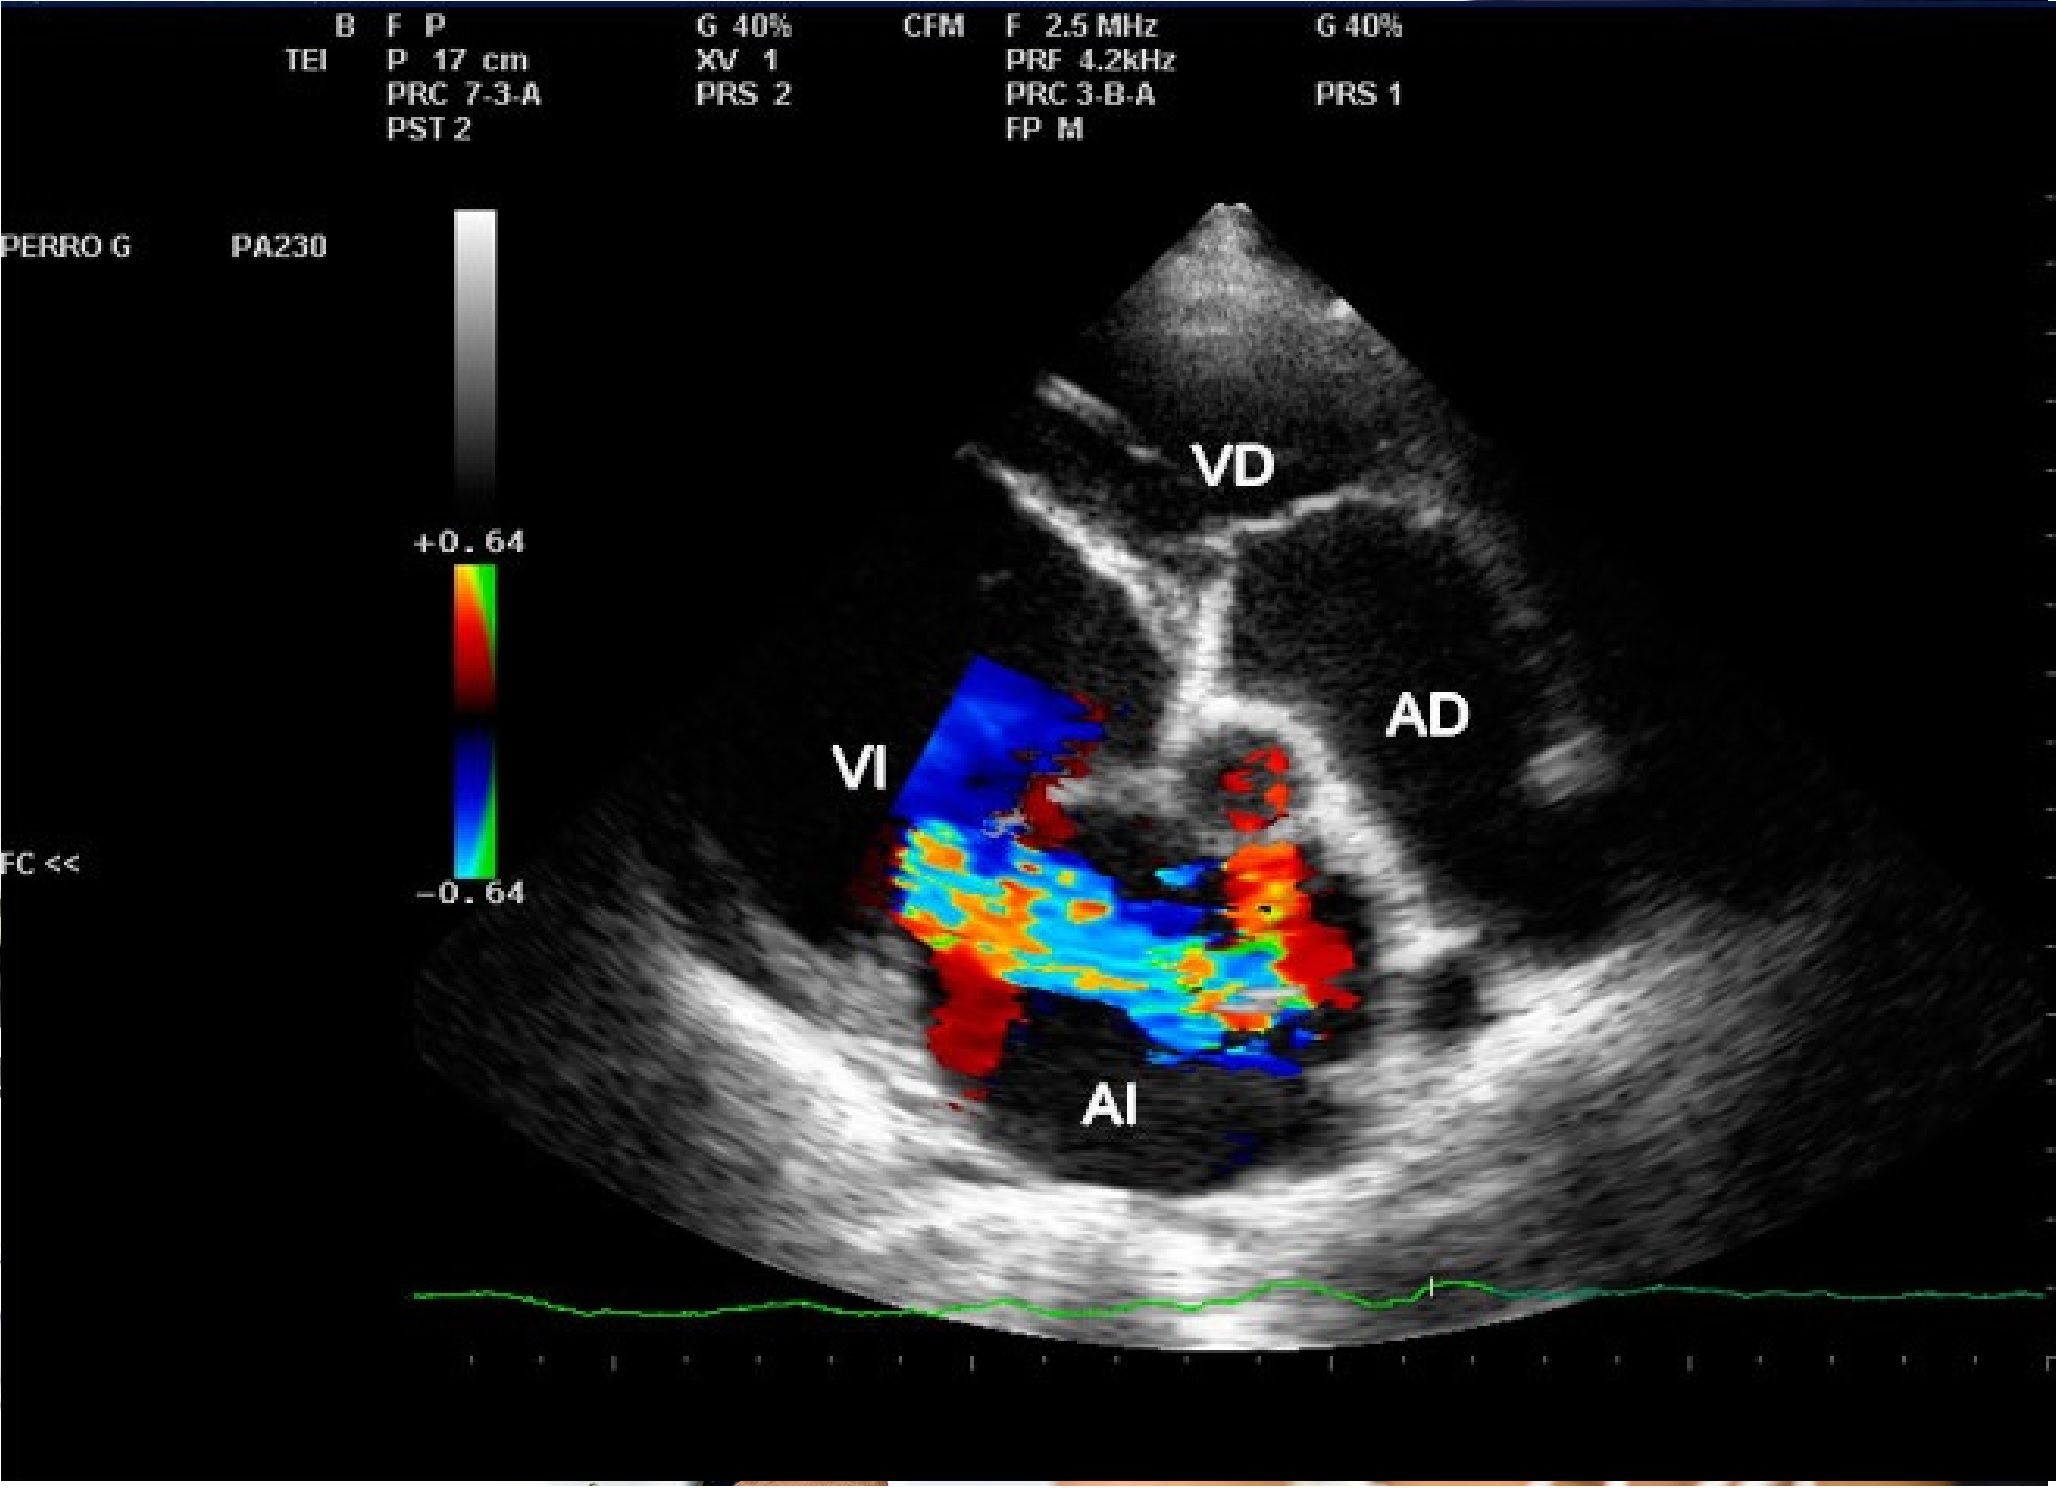

La ecografía es una técnica de diagnóstico por imagen no invasiva que utiliza ondas de ultrasonido para visualizar en tiempo real órganos, tejidos blandos y estructuras internas del cuerpo. A diferencia de otros estudios, no emplea radiación, lo que la convierte en una herramienta segura, ampliamente utilizada en diversas áreas médicas para detectar alteraciones, monitorear enfermedades y apoyar decisiones clínicas con agilidad y precisión.

En SCANNER S.A. contamos con equipos ecográficos de alta resolución, diseñados para ofrecer imágenes claras y detalladas. Nuestro servicio incluye tanto ecografía general como ecografía especializada, permitiendo realizar estudios abdominales, pélvicos, ginecológicos, obstétricos, renales, tiroideos, de partes blandas, musculoesqueléticos y más.